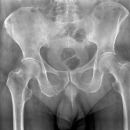

Fraktur Ramus pubis sup. und inf.

Open Book Fracture